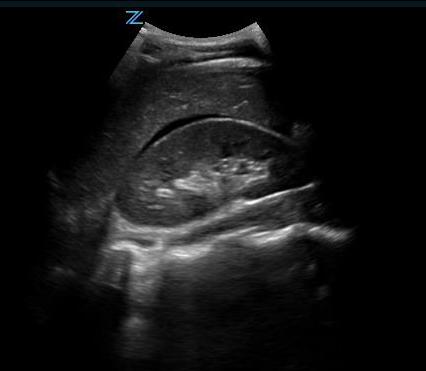

- Pelvic Views

- Pelvic views are not as easy to obtain as right upper quadrant views, but since the pelvis is the most dependent part of the peritoneal space, it is the most likely place to see abdominal free fluid.

- Place the probe in the midline just cephalad to the pubic bone with the transducer indicator pointed cephalad. Make sure the probe position is correct by actually placing the probe on the pubic bone and noting a bone shadow on the image. (Fig. 14) From this position sliding the probe slightly cephalad will produce a longitudinal pelvic view.

- The bladder will be found just cephalad to the pubic bone and can usually be found even if it is nearly empty. A full bladder will be triangular in shape. The lower angle of the bladder marks the border between the intraperitoneal space (left side of the image) and the true pelvic structures (right side of the image).

- In a male, free fluid will be seen along the inferior peritoneal cavity just posterior to the wall of the bladder.

- In a female, the body of the uterus sits in the intraperitoneal space just posterior to the bladder (Video 19), so free fluid will be seen just posterior to the uterus, also known as the pouch of Douglas. A trace amount of free fluid can be normal in the pouch of Douglas depending on the woman’s menstrual cycle. Free fluid often is seen here first. (Video 20) Free fluid may also be seen completely surrounding the edges of the uterus. (Video 21) If there is clot in the pelvis, this will look grey compared with unclotted blood which will be black. (Video 22)